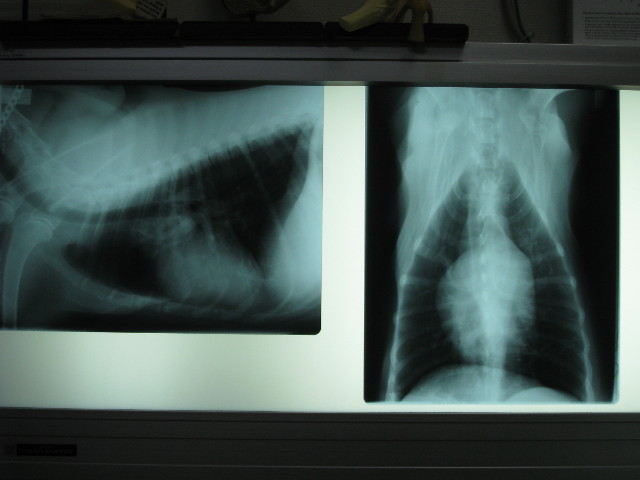

ベベはレントゲンなど撮ってなんやかんやステロイドを打ったのはお昼頃だった。

【2008年3月16日のステロイド投与2時間後の動画】